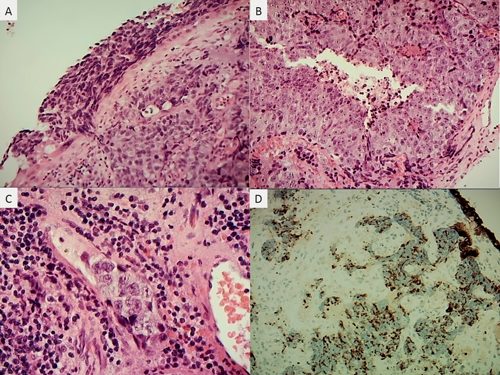

A tale of two membranes

It was the best of times, it was the worst of times... It was the season of Light, it was the season of Darkness... I am fortunate to work on a vitreoretinal firm at the moment and only a few...